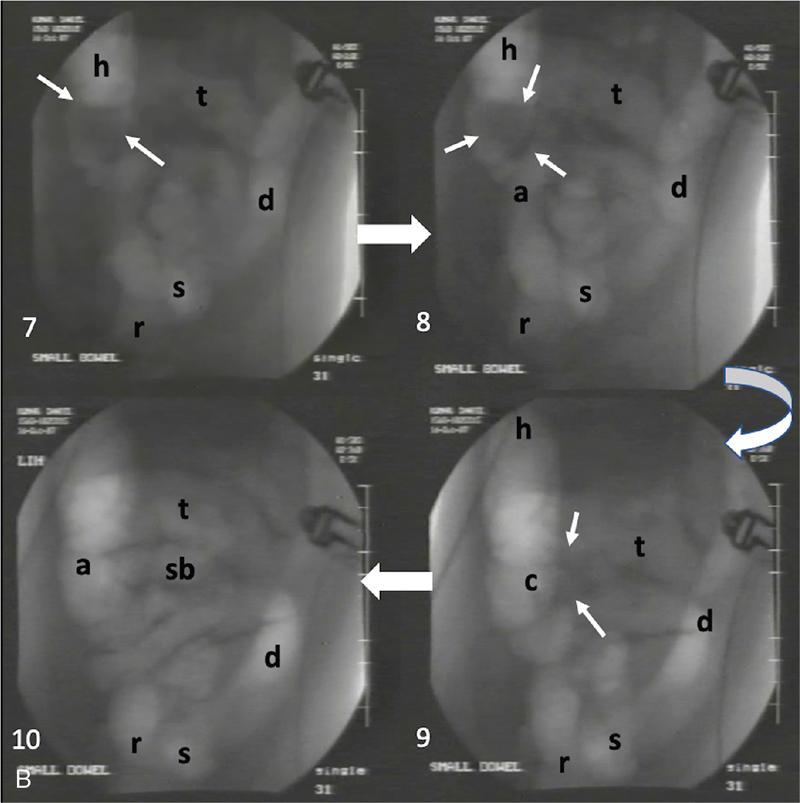

Ajay Taranath, Lino Piotto Intussusception is a common cause of acute abdominal pain in children. In this condition, a portion of the bowel wall, the intussusceptum, invaginates into the lumen of the portion of the bowel immediately distal to it, the intussuscipiens. It occurs most commonly in the first two years of life but is sometimes seen in older children. Once the invagination process has begun, the first part of the intussusceptum (the head) is pushed distally by peristalsis dragging the wall of the bowel with it. This tends to be progressive once it starts and as the invagination continues, interference with the blood supply of the intussusceptum causes venous occlusion and subsequent mucosal congestion. In advanced cases, the vascular compromise may result in the passage of blood-stained mucus through the rectum (red-currant jelly). Intussusception may be idiopathic or may be due to a pathologic ‘lead point’ such as a Meckel’s diverticulum, duplication cyst or neoplastic mass within the bowel wall. Most patients under the age of 2 years are in the idiopathic group. These are thought to be associated with thickening of bowel wall caused by hyperplasia of Peyer’s patches in response to a recent viral infection. Pathologic lead points are much more common in patients older than 4 years. For this reason, the head of the intussusceptum in these patients should be scanned carefully for evidence of a lead point. Intussusception is usually described according to the bowel that is involved. Those involving only small bowel include jejuno-jejunal (jejunum into jejunum) and ileo-ileal (ileum into ileum), are often seen as an incidental finding in abdominal sonography and only infrequently require intervention, when they have caused a bowel obstruction (Fig. 7.12.1A and B). Those involving large bowel include ileo-colic (ileum into colon), ileo-ileo-colic (ileum into ileum and then into colon) and colo-colic (colon into colon) and almost always require intervention. The most common of these is the ileo-colic type, in which the terminal ileum invaginates the colon through the ileo-caecal valve. The longer the intussusception persists, the greater the likelihood of gut necrosis and the need for surgical resection. Typically, children with intussusception will present with some or all of the following clinical features: attacks of colic, vomiting, blood and mucus per rectum, palpable abdominal mass. The attacks of colic are often associated with drawing-up of the legs. The duration of symptoms is usually less than 48 hours. The peak incidence is around 18 months though it can occur in children as young as 5 months and as old as 15 years. Traditionally, children suspected of suffering from an ileo-colic intussusception would be investigated with supine, erect and occasionally prone plain radiographs. When the clinical suspicion was high, the only way to confirm or exclude the presence of an intussusception was to perform a barium enema. A hydrostatic reduction using barium would then be employed to reduce an ileo-colic intussusception if one was found. More recently, pneumatic reductions have become the method of choice in many departments; benefits of this method include excellent reduction results and less radiation exposure than a barium enema. Pneumatic reductions have also shown to have greater reduction success rates than with barium. However, depiction rates of a pathological lead point on air enema are poor. Navarro et al. demonstrated a depiction rate of 11% in their study. Miller et al. showed a slightly higher depiction rate of 16%. Also, it must be noted that a successful reduction by an air enema cannot exclude a pathological lead point. In particular, lesions within the small bowel can be overlooked. Reduction rates also diminish when a pathological lead point is involved. Navarro et al. achieved a reduction rate of 29% in children presenting with their first episode of intussusception resulting from a pathological lead point. The relatively high-radiation dose from enema reductions was a significant factor in the development of ultrasound techniques, initially used only to identify those patients who had intussusception and therefore required a reduction. As a natural progression, the use of ultrasound in some institutions has been extended to monitoring of the reduction procedure. It is very important that the patient is well hydrated. It would be beneficial to have an intravenous access in all the patients with ileo-colic intussusception needing a pneumatic reduction. Administration of antibiotics may need consideration to ward off complications that might arise if there was an inadvertent perforation. It would be helpful to administer analgesics in consultation with the surgical team to help obtain compliance. The paediatric surgeon is in attendance. An 18 g cannula is kept handy to release the free air if a perforation occurs during the attempted reduction. The setup for a pneumatic reduction of intussusception (Fig. 7.12.2) consists of the following: (i) A cylinder of sterile medical air. (ii) A tube that leads away from the cylinder to a pressure limiting chamber. It has a dial indicating the pressure and a valve at the top of the chamber that will open if the pressure attained intraluminally goes over what has been set. (iii) A tube leading from the pressure-limiting chamber to a Foley’s catheter that is placed in the rectum. (iv) A three-way Y-valve (that can be controlled by the operator’s thumb in case the pressure control needs to be achieved quickly) is interposed midway in the tube leading out of the pressure chamber. It is important to get a good seal at the rectum. The chamber pressure is set at 80 mm Hg at the start of the reduction. A thumb rule of 3 is followed in that if there is no success with reduction after employing a pressure of 80 mm Hg for 3 minutes, it is increased to 100 mm Hg for 3 minutes and if the operator is comfortable, to 110–120 mm Hg for 3 minutes. If reduction is not achieved, surgical intervention may need to be considered in consultation with the paediatric surgeons. The air insufflation is begun. Retrograde movement of the intussusceptum is tracked fluoroscopically. There may be a point when the intussusceptum reaches the ileo-caecal junction and fails to respond to the air insufflation. It would helpful for the patient as the ileo-colic intussusceptions without pathological lead points tend to reduce, albeit in a delayed manner. The procedure is concluded when the insufflated air enters the small bowel loops (Fig. 7.12.3A and B).